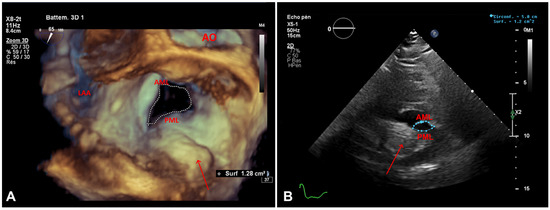

Myocardial infarction with nonobstructive coronary arteries (MINOCA): Myocardial infarction (MI) with non-obstructive coronary arteries (MINOCA) is defined as MI according to the fourth universal definition of MI [1] without coronary stenosis ≥50% on...